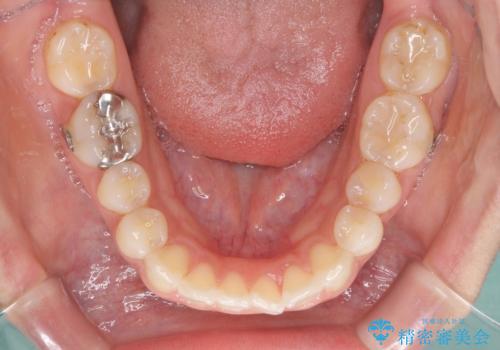

- 上の前歯の捻じれと突出感を気にして来院された患者様です。

目立たない装置を希望とのことで、上顎左右第一小臼歯を抜歯し、インビザラインにて矯正治療を行うこととしました。